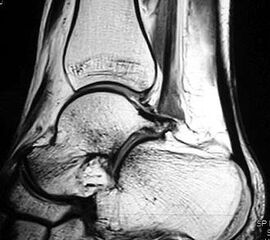

Z.n. Distorsion des Fußes mit „Ruptur“ der (vorbestehenden) talocalcanearen Coalitio. Die Wassereinlagerung in den an die Coalitio angrenzenden knöchernen Bezirken ist im MRT gut zu erkennen. Nach monatelangen Beschwerden spontane Besserung.

MRT und CT konkurrieren in der Fein-Darstellung der Knochenbrücke, der Beurteilung der nichtbetroffenen Anteile des Subtalargelenkes und der Sekundärveränderungen. Das MRT bietet den Vorzug, bindegewebige und knorpelige Strukturen (Abb. 2) und bei Einsatz von Kontrastmittel auch knöcherne Aktivierungsphänomene genau abzubilden; die knöcherne Feinstruktur und genaue Ausdehnung dagegen ist mit dem Dünnschicht-CT wesentlich exakter darstellbar (Abb.3). In manchen Fällen ist eine 3-D-Rekonstruktion des CT hilfreich. Besonders wichtig ist eine geeignete Schichtebenen-Wahl:

Die zweite wichtige Form tarsaler Coalitiones findet sich im medialen Bereich des Subtalargelenkes, am häufigsten unter Einbeziehung der medialen, mittleren Facette des talocalcanearen Gelenkes (Abb. 9). Die Ausdehnung der zunächst fibrösen, später zunehmend verknöcherten Brückenbildung kann sehr unterschiedlich Anteile der hinteren Kammer des unteren Sprunggelenkes mitumfassen; auch rein dorsomediale Formen ohne Einbeziehung der medialen Facette werden beobachtet (Abb. 2) 67 (Hamel 2008).

Diagnostisch sollte neben Röntgenübersichtsaufnahmen (indirekte radiologische Zeichen: Dorsaler Traktions-Osteophyt am Taluskopf, „talar beaking“; kontinuierliche Linie der Trochlea-tali-Kontur übergehend in die Sustentaculum-tali-Kontur, „C-Zeichen“ (Abb. 11) 10) immer die dreidimensionale Bildgebung eingesetzt werden. Das MRT (mit Kontrastmittel) kann die Struktur der Brückenbildung und z.B. die Qualität des Restgelenkes (Knorpel-Dicke) besonders gut abbilden; das Dünnschicht-CT zeigt die knöcherne Feinstruktur im Bereich der Coalitio und den oft sehr schrägen Spalt-Verlauf im Frontalschnitt dagegen häufig genauer. Meist findet sich die Überbrückung im Bereich der medialen Facette; die Schichten sollten jedoch bis weit nach dorsal beurteilt werden, da ansonsten dorsomediale Formen übersehen werden können. Rozansky et al 7 unterschieden fünf morphologische Typen auf der Basis von 3-D-CT-Rekonstruktionen. Allerdings ist eine prognostische Zuordnung bisher nicht möglich.